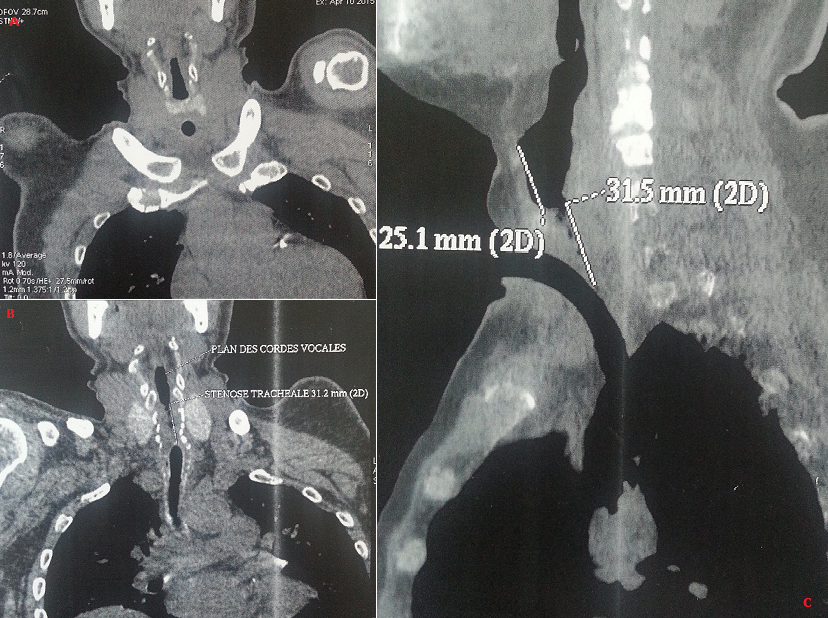

La fréquence des sténoses trachéales post-intubation (STPI) varie selon les études de 10 à 22 %. Seulement 1 à 2% de ces sténoses sont sévères ou symptomatiques et se manifestent par un tableau de dyspnée inspiratoire ne cédant pas sous traitement corticoïde. Les STPI surviennent souvent chez des patients à l'état général altéré, ce qui complique leur prise en charge. Nous rapportons le cas d'un patient âgé de 43 ans, hypertendu, qui a présenté il y a un an un Accident Vasculaire Cérébral hémorragique suite à un pic hypertensif avec un coma ayant duré 3 mois nécessitant une intubation prolongée et une trachéotomie. Une décanulation s'est avérée impossible à maintes reprises, se soldant à chaque tentative de décanulation par une détresse respiratoire. L'examen ORL spécialisé avait révélé une sténose importante sous glottique au-dessus de l'orifice de trachéotomie. Le TDM a confirmé la sténose trachéale (A, B, C). Une trachéoscopie sous anesthésie générale avait mis en évidence une sténose sous glottique à un cm du plan glottique. Le patient a été opéré et a eu une résection trachéale proximale de trois cm avec une mucosectomie cricoïdienne postérieure et une anastomose crico-trachéale. L'évolution post-opératoire était favorable. Le diagnostic de STPI est parfois difficile mais il doit être évoqué chez tout patient aux antécédents d'intubation et/ou de trachéotomie présentant une dyspnée d'apparition récente ou inhabituelle. La résection-anastomose trachéale, telle qu'elle a été faite pour notre patient, reste le traitement de référence.